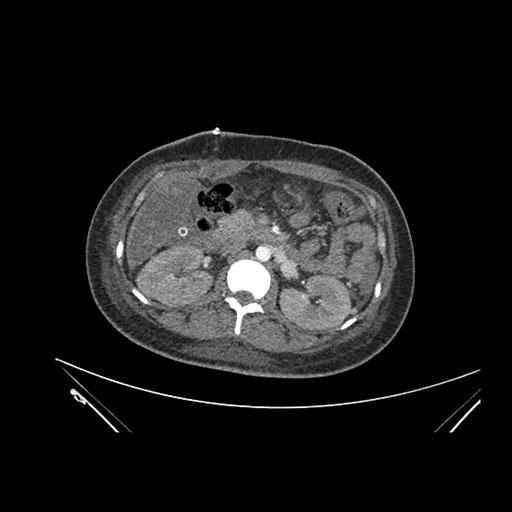

Imaging Analysis

Look through the patient's CT scan to identify any areas of concern for the necessary procedure.

Axial Arterial

Based on initial findings, which issue(s) would you be most concerned about?